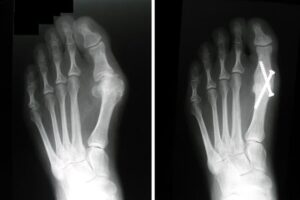

You may require several preoperative tests, including blood counts, an echocardiogram, and a chest X-ray. You may also need to provide a urine sample.To help plan your procedure, your doctor may order special foot X-rays. These X-rays should be taken in a standing, weightbearing position to ensure your doctor can clearly see the deformity in the foot. These special X-rays assist your doctor in making decisions about where along the bone to perform an osteotomy to provide enough corrective power to straighten the toe.

An osteotomy is a surgical procedure in which your doctor makes precise cuts in the bones to realign the joint and correct the bunion deformity. After cutting the bone, the newly adjusted position is stabilized using pins, screws, or plates. This realignment ensures the bones are straighter and the joint is properly balanced.How Osteotomy Works

- Bone Realignment: Osteotomies can be performed at different points along the bone, depending on the severity and location of the deformity.

- Bone Wedge Removal: In some cases, a small wedge of bone may be removed to provide additional correction and straighten the toe effectively.

Because bunions vary in shape and size, there are different surgical procedures performed to correct them. In most cases, bunion surgery includes correcting the alignment of the bone by cutting and shifting the bones. This will most likely require the placement of surgical hardware (plates and screws) as well as repairing the soft tissues around the big toe. Your doctor will talk with you about the type of surgery that will best correct your bunion.